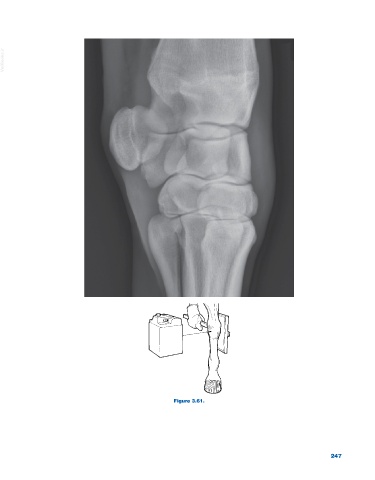

Figure 3.61.